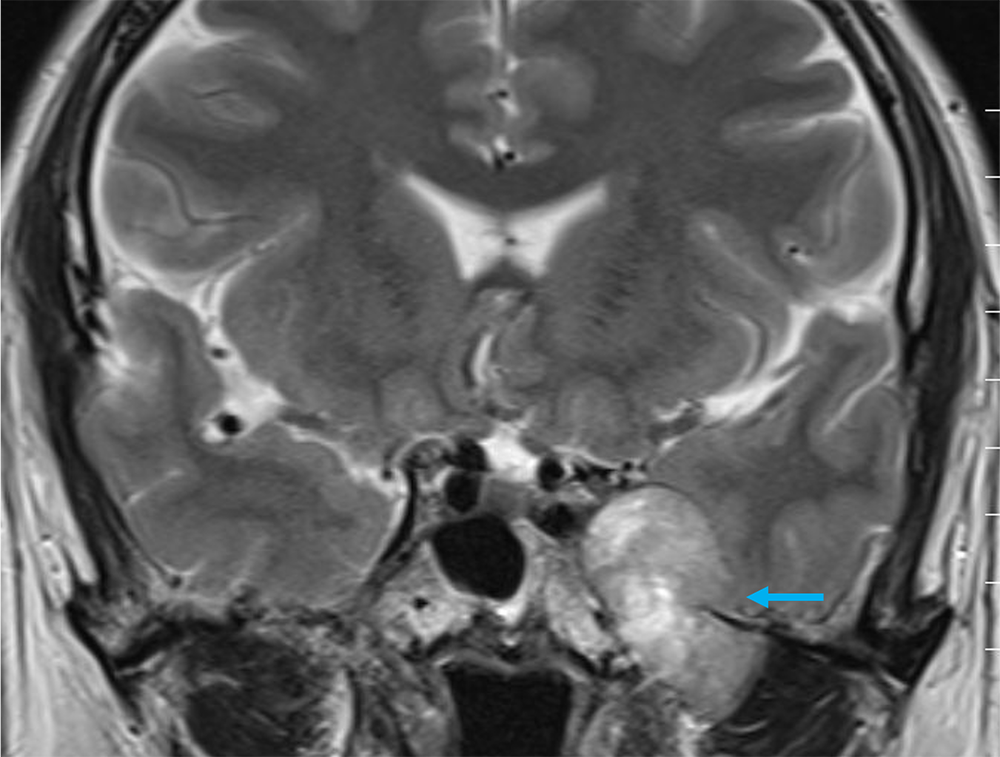

単純MRIのT2強調画像では左メッケル腔から背側に突出する腫瘍を認め、三叉神経鞘腫と髄膜腫が鑑別となる。Gd造影剤の脂肪抑制T1強調画像では腫瘍は全体に濃染し、冠状断では卵円孔を介した頭蓋外進展が見られ、三叉神経鞘腫の可能性が高い。内側では海綿静脈洞を圧排、背側では橋の軽度圧排も見られる。有症状であり、手術が施行され、三叉神経鞘腫と診断された。